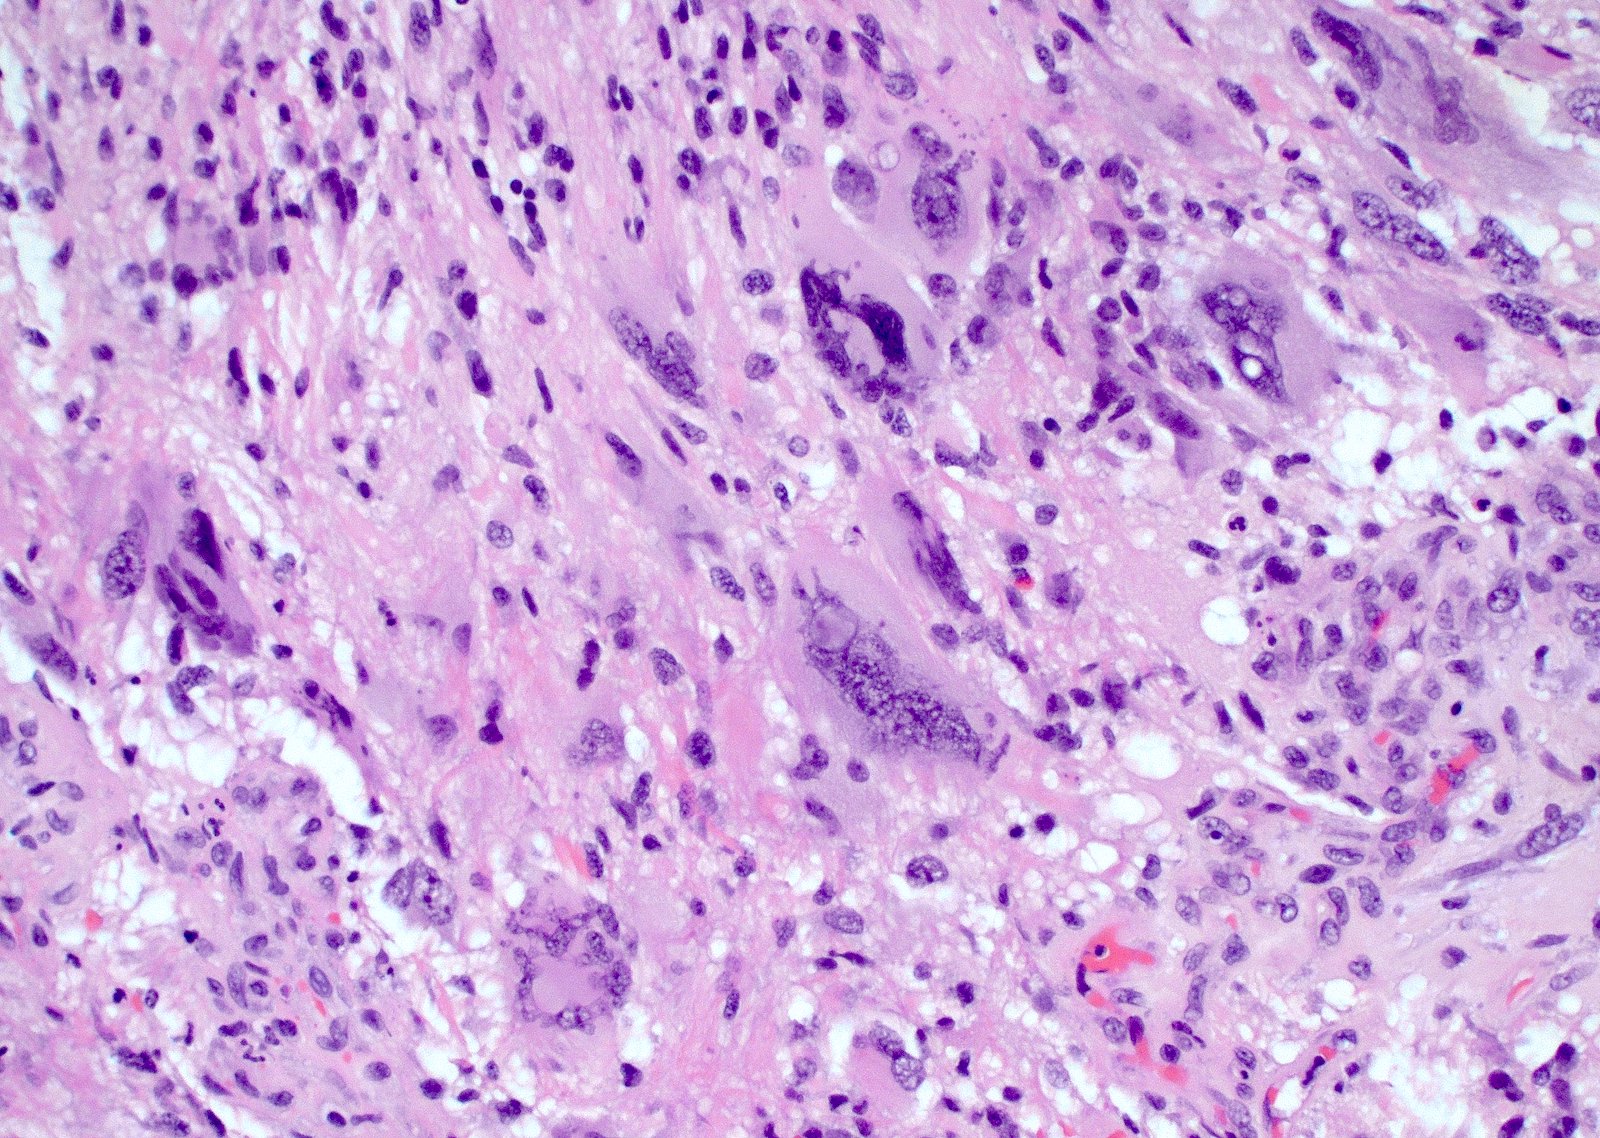

Microscopic (histologic) description

- Infiltrating, hypercellular astrocytic neoplasm often with hyperchromatic, elongated nuclei and irregular nuclear membranes

- Microvascular proliferation or necrosis is required for a histologic diagnosis of GBM

- Microvascular proliferation: multilayered, small caliber vessels with glomeruloid appearance (J Neuropathol Exp Neurol 1992;51:488)

- Necrosis: can be geographic or pseudopalisading with neoplastic cells surrounding central necrosis

- Greater association of thrombosis and necrosis in IDH wild type GBM than in IDH mutant grade 4 astrocytomas (Acta Neuropathol 2016;132:917)

- Variable cell morphology: undifferentiated / primitive neuronal cells, astrocytic, gemistocytic, oligodendroglial-like, small cell, lipidized, granular, epithelioid, giant cells, mesenchymal metaplasia and epithelial metaplasia

- Mesenchymal / sarcomatous: may be well circumscribed; corresponds to cellular differentiation along various lineage; sarcomatous (spindled and fibroblastic), osseous, chondroid or myogenic differentiation (see Gliosarcoma)

- Sarcomatous component usually comprised of GFAP negative spindled cells with reticulin deposition rich

- Associated with mutations in TP53, PTEN, TERT and CDKN2A deletion and MDM2 and CDK4 coamplification (J Neuropathol Exp Neurol 1995;54:651, Am J Pathol 2000;156:425, Acta Neuropathol 2001;101:321)

Microscopic (histologic) images

Contributed by Bharat Ramlal, M.D. and Meaghan Morris, M.D., Ph.D.